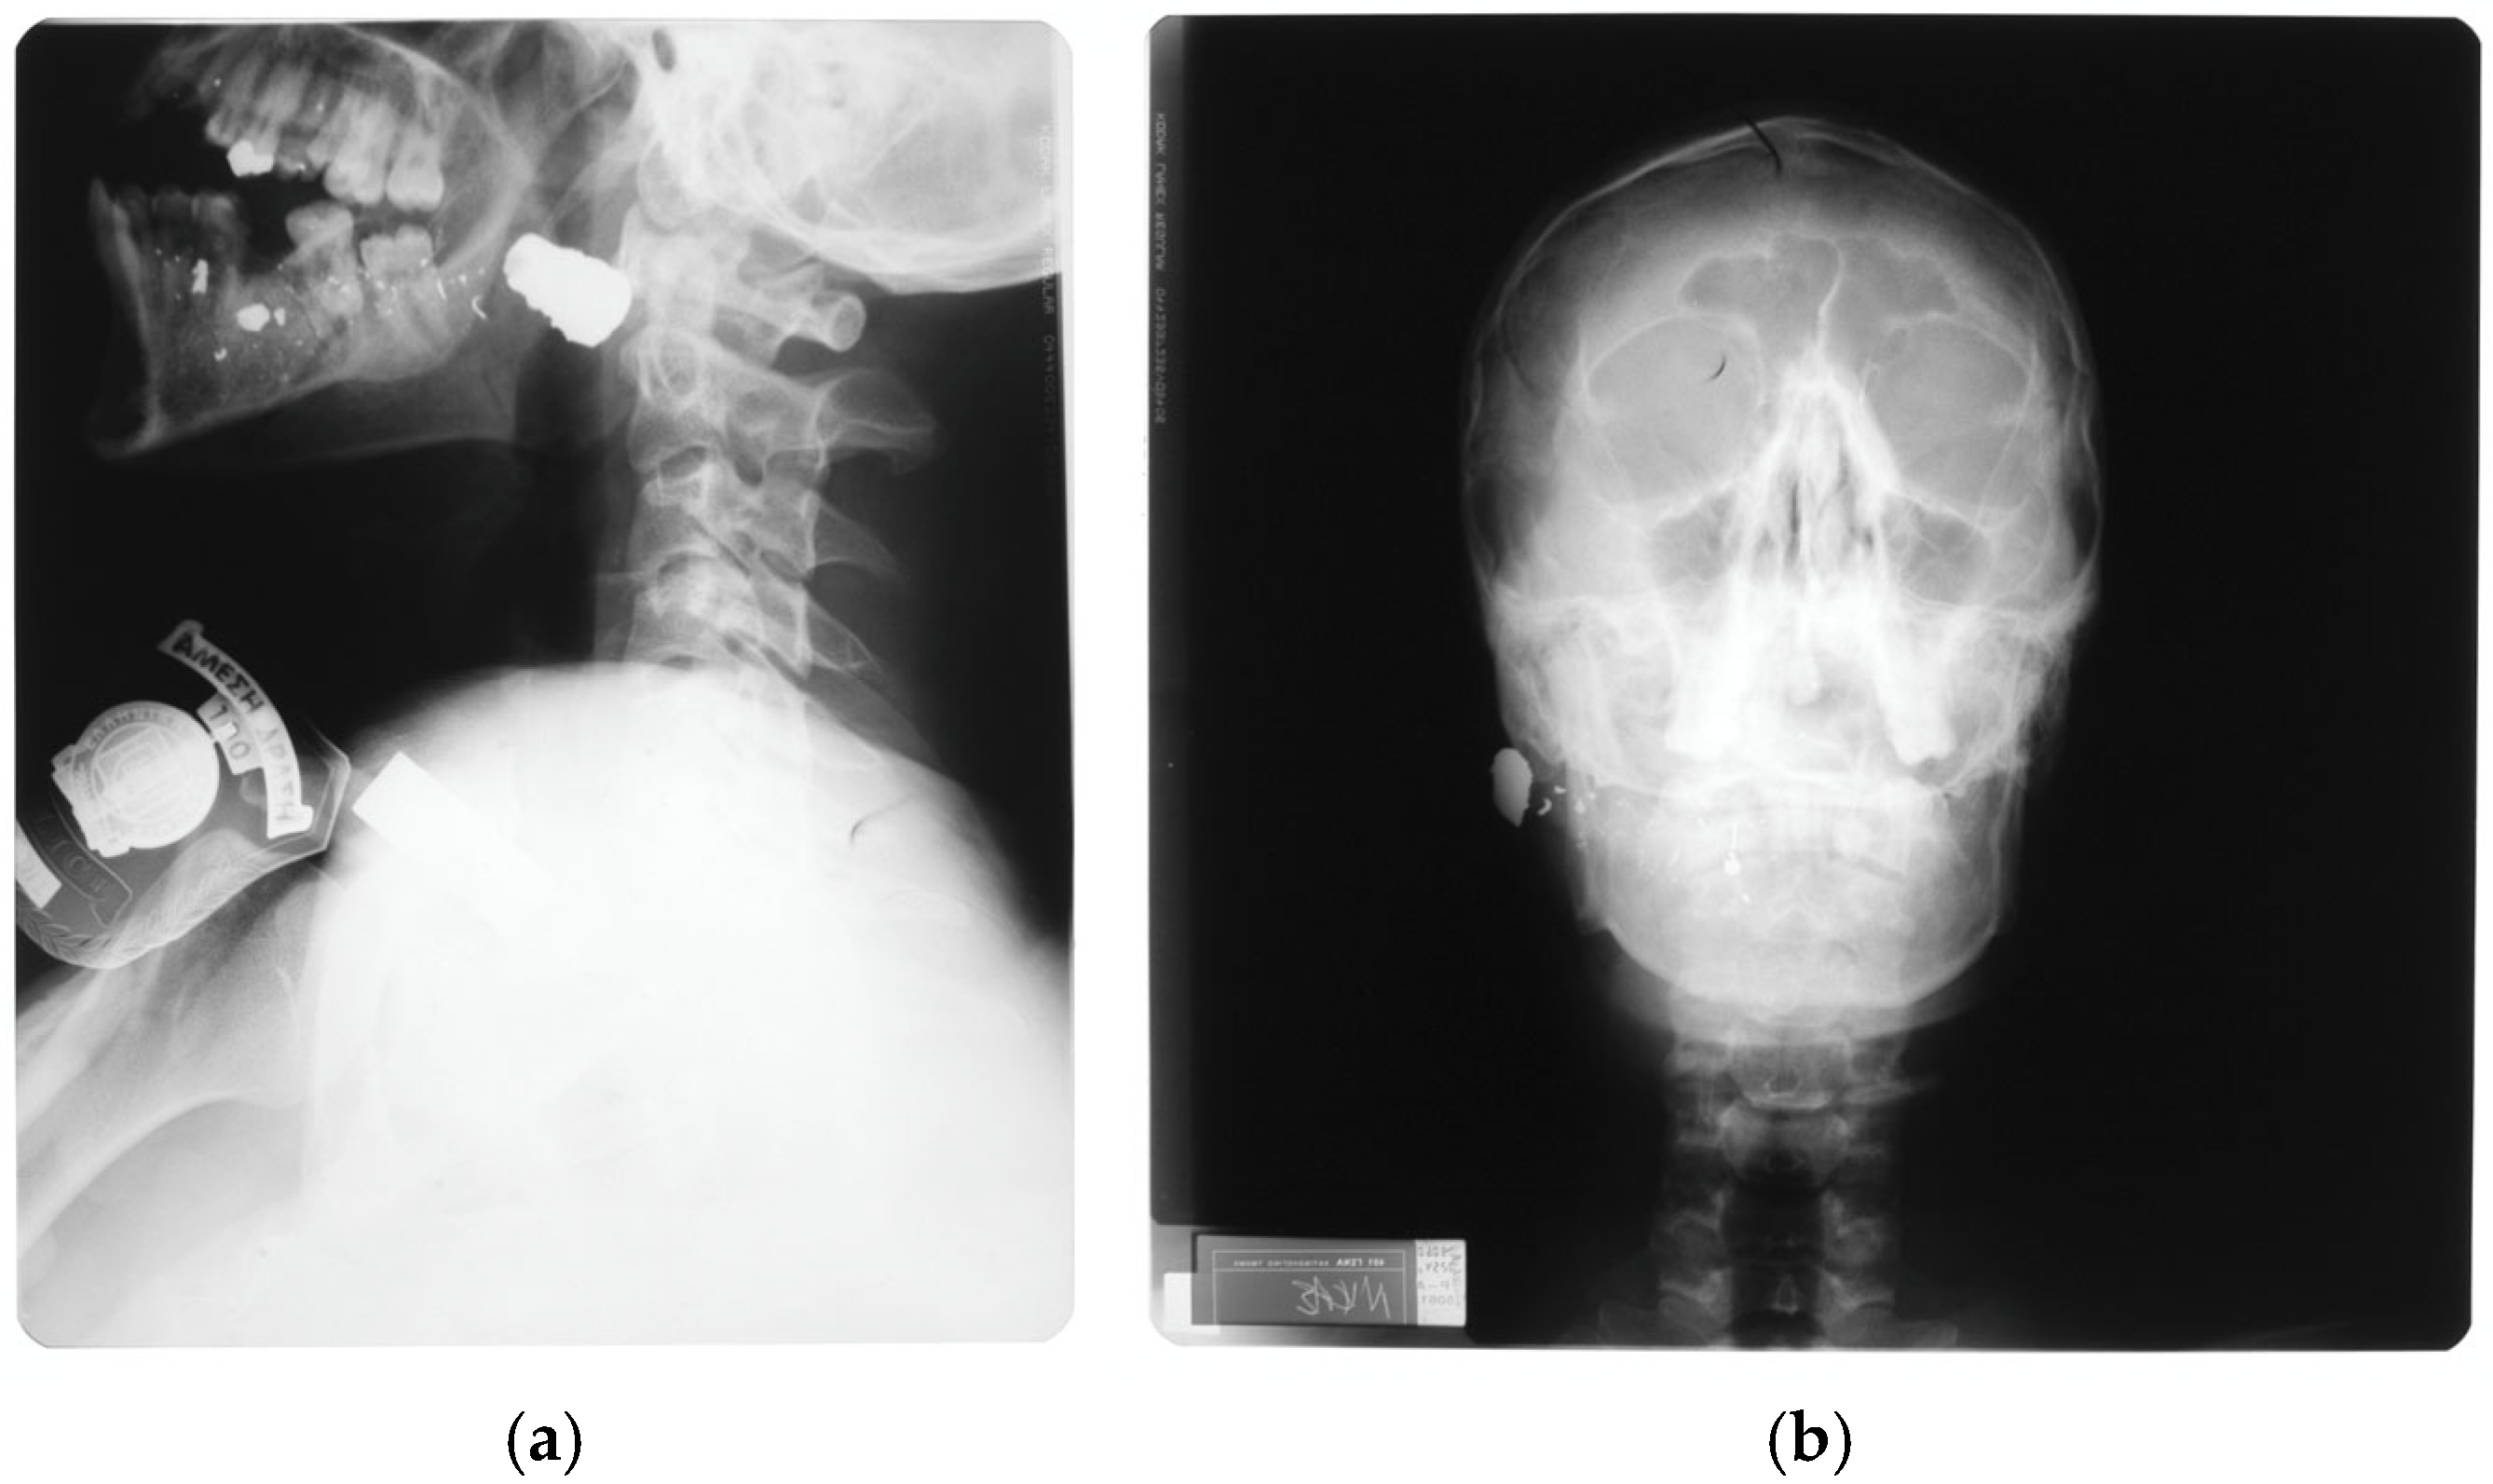

- Oehmichen, M.; Meissner, C.; König, H.G.; Gehl, H.B. Gunshot injuries to the head and brain caused by low-velocity handguns and rifles: A review. Forensic Sci. Int. 2004, 146, 111–120. [Google Scholar] [CrossRef]

- Majors, J.S.; Brennan, J.; Holt, G.R. Management of high-velocity injuries of the head and neck. Facial Plast. Surg. Clin. North. Am. 2017, 25, 493–502. [Google Scholar] [CrossRef]